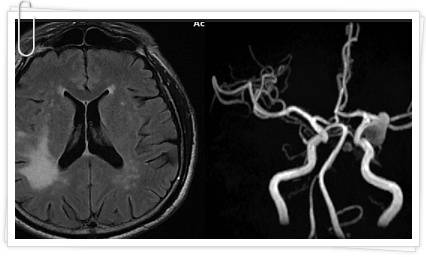

뇌졸중이란 우리 뇌에 있는 경우 혈관의 일부가 막혀서 막힌 부위의 뇌세포와 신경이 죽는 질환이라고 말할 수 있어요. 뇌는 혈액과 산소를 계속해서 공급받아야만 하며 뇌로 가는 혈액 공급이 차단되면 매우심각한 상황에 빠질 수 있으며 처치가 늦어지면 목숨을 잃을 수도 있어요. 뇌경색 초기증상을 알고 있어서 증상이 나타날 경우에는 빠른 시간 병원을 방문하셔서 처치를 받으시는 게 좋을 것 같아요.

뇌졸중은 뇌혈관이 물리적 장애로 인해 막힐 때 발생해요. 이것은 일반적으로 나이로 인해 동맥이 경화되거나 심장이 심장 질환으로 고통받을 때 발생한다고 해요. 뇌졸중의 증상은 당뇨병, 콜레스테롤 상승 또는 고혈압에 의해 악화될 수 있으며 환자는 나이가 들고 추운 날씨에 노출되었을 때 광범위한 혈관 질환의 일종으로 이런 증상을 경험해요. 뇌의 특정 부분에 영향을 미칠 때 뇌졸중은 한쪽 사지와 신체의 한쪽 면에 마비를 유발할 수 있어요.

뇌경색이 생긴 것을 모르고 있다가 건강검진이나 다른 질환을 검사하다가 우연히 뇌경색을 발견하는 경우가 있습니다. 무증상 뇌경색이 발병하기 쉬운 고혈압, 비만, 당뇨, 가족력 등의 위험 인자가 있으면 정기적인 검사를 받으셔서 건강관리를 미리 해주시는 것도 좋은 방법인것 같습니다.